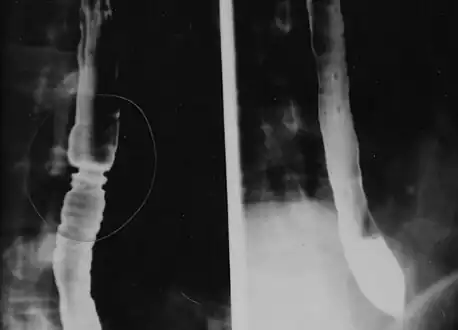

Radiologically, the term "ringed esophagus" has been used for the appearance of eosinophilic esophagitis on barium swallow studies to contrast with the appearance of transient transverse folds sometimes seen with esophageal reflux (termed "feline esophagus").[19]

The barium swallow of the esophagus on the left side shows multiple rings associated with eosinophilic esophagitis.